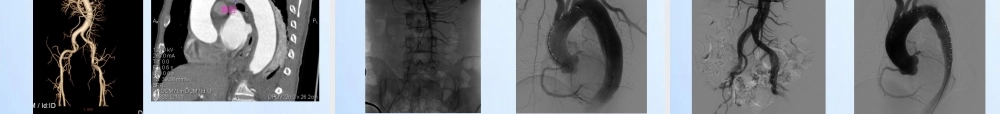

急性StanfordB型AD并灌注不良的处理南昌大学第二附属医院血管外科周为民,周卫、邱结华、袁庆文、陈锋、熊吉信E-mail:drzwm@sina.comTel:13870658585概述急性B型主动脉夹层的假腔可以压迫从腹主动脉发出的动脉分支,导致急性肾功能不全,缺血性肠炎、肠坏死,肝功能衰竭,下肢动脉缺血甚至坏死TEVAR不仅可以封堵主动脉夹层的破口,而且还可以缓解假腔对分支动脉的压迫,使闭塞的分支动脉重新开放作者自2003年7月至2013年11月共收治主动脉夹层208例,其中35例主动脉夹层合并有内脏缺血和下肢动脉缺血或坏死,分别通过TEVAR术及分支动脉支架、导管溶栓和截肢术等方法治疗,取得较好的效果研究目的•评估急性StanfordB型主动脉夹层并内脏或下肢动脉灌注不良的腔内治疗的可行性、疗效和近中期结果研究方法回顾性分析作者自2003年7月-2013年11月间收治的35例急性B型AD并内脏或下肢动脉灌注不良患者的临床资料术前术中术后均经CTA和DSA确诊临床资料男32例,女3例,年龄42-75岁,平均52.5±8.6岁病程4h-14天,均有高血压病史13例(37.1%)SMA缺血,9例(25.7%)肾动脉缺血,5例(14.3%)腹腔干缺血,8例(22.9%)下肢缺血(左下肢坏死1例),3例同时有肾动脉及下肢动脉缺血结果4例分别于左锁骨下动脉和腹腔干之间放置2个支架人工血管6例采用LSA烟囱技术9例因肠系膜上动脉缺血而植入支架(6例)或导管溶栓(3例)1例远端假腔内血栓形成压迫右髂动脉致其闭塞,TEVAR术后于右髂动脉内植入裸支架1枚1例合并左下肢动脉缺血坏死TEVAR术后一期行左大腿中上段截肢术首先TEVAR封堵第一破口结果•14例TEVAR后假腔消失,内脏血管恢复真腔供血,闭塞髂动脉真腔开放•技术成功率100%•随访1周-72个月,平均21.4±11个月,无移植物移位及器官缺血•灌注不良动脉支架通畅率100%Case1术前CTASMA术前CTA术中DSA造影TEVAR后造影假腔消失,SMA未见明显显影SMA支架术后造影SMA术后6月CTA复查SMA支架SMASMACase2真腔狭小,SMA双腔供血真腔CTATEVARbeforeafterTEVARbeforeafterCase3真腔闭塞CTA真腔闭塞CTA破口假腔真腔beforeTEVARbeforeTEVARafterafterCase4TEVAR+SMACDTTEVAR+SMACDTFollow-up5dFollow-up2moFollow-up12moCase5主动脉夹层并左髂动脉闭塞,左下肢严重缺血CTA在髂动脉闭塞TEVAR+截肢beforeafterCase6右髂动脉闭塞CTA右髂动脉未显影DSA评估TEVAR+chimney术后造影Follow-up1W术后1周仍有右下肢缺血右髂动脉stentSTENT:8mmx150mm,LUMI...